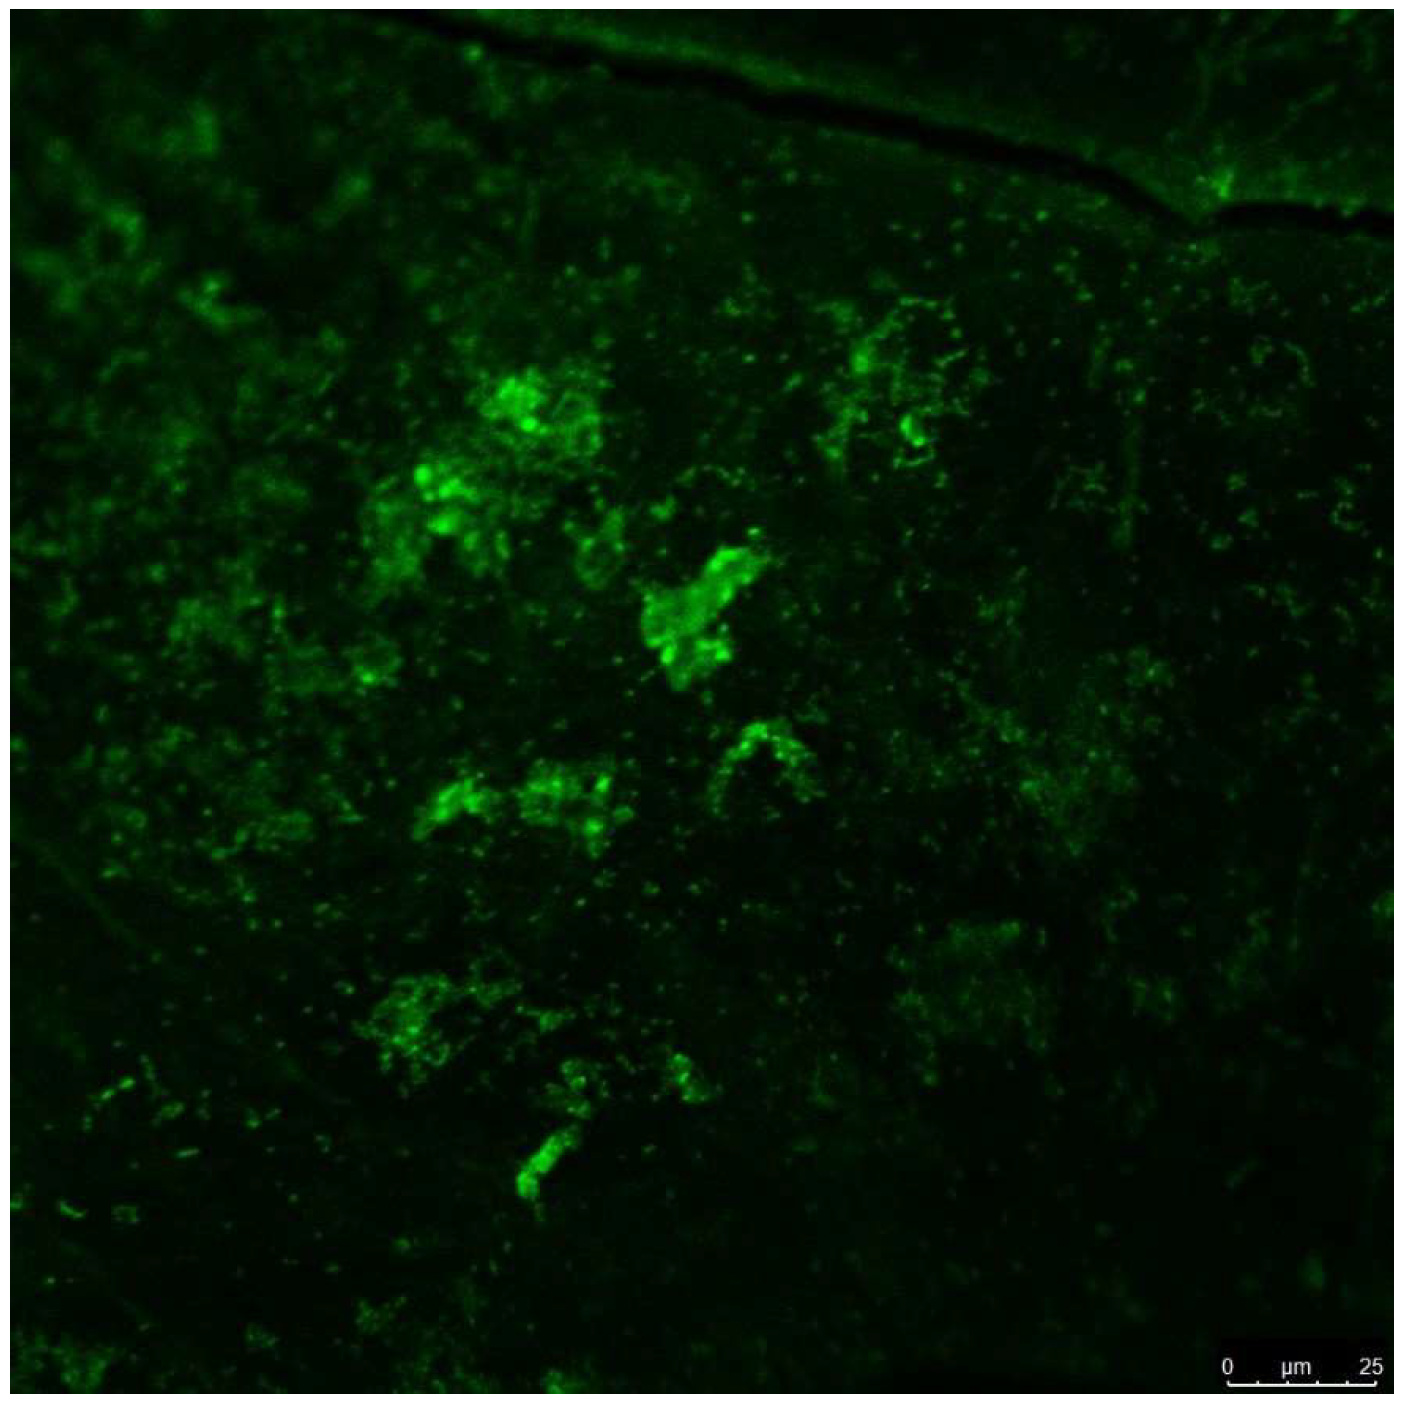

3.2. Qualitative Results of Scanning Electron Microscopy and Confocal Laser Scanning Microscopy